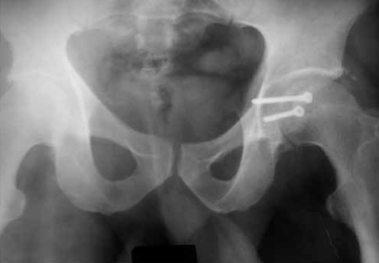

Большая, средняя и малая ягодичные мышцы вместе с грушевидной отводятся кверху, верхняя близнецовая — книзу. Следует помнить о выходе из малого таза седалищного нерва под грушевидной мышцей в проксимальном ее участке. Также производится ревизия состояния хряща головки бедренной кости, отломка, установка его после промывания полости сустава, стабильная фиксация с элементами компрессии (рис. 5, 6).

Обзорная рентгенограмма таза. Состояние после открытой репозиции и фиксации среднего отдела заднего края вертлужной впадины 2 винтом. Стабилизация и разгрузка тазобедренного сустава в аппарате внешней фиксации

Рентгенография тазобедренного сустава в двух проекциях (прямая и аксиальная). Срок после оперативного лечения — 3 года